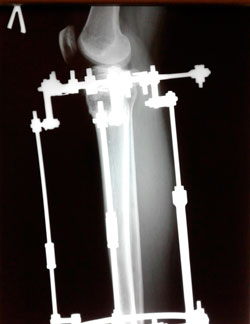

Перед снятием аппаратов

Дата операции - 04.06.2020

Дата снятия аппаратов 13.10.2020